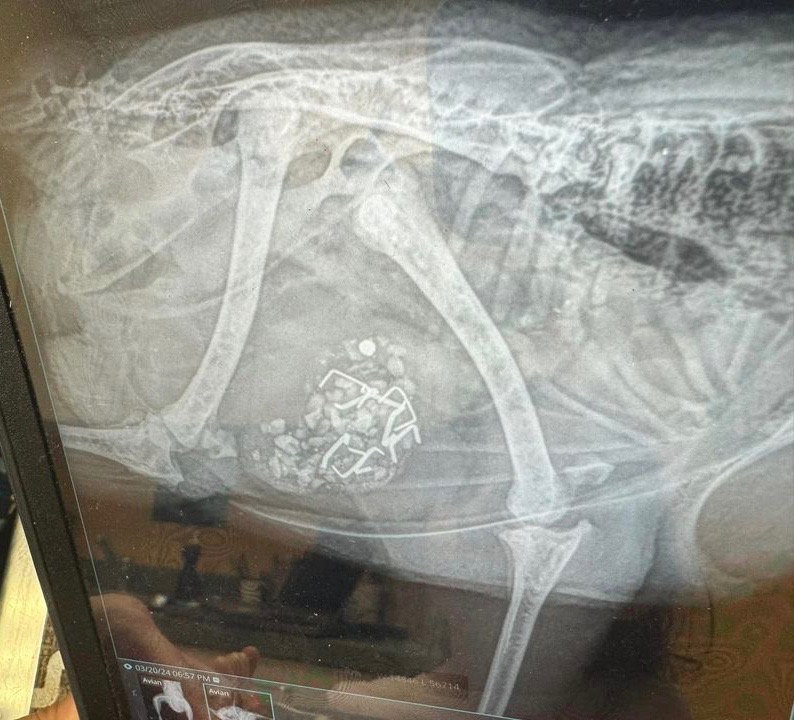

Foreign Body Ingestion

I noticed one hen laying down and not getting up. I found what I thought was broken yolk on her feathers around her bottom. I ultimately assumed an egg broke in her which I’ve dealt with many times. I scheduled emergency vet appointment with our avian vet for 6 pm. By then her leg is splayed out to the side, she’s deteriorated and seems more uncomfortable and won’t stand. They do X-rays and vet comes back in and says she has good and bad news (which should have been good and worse news). She didn’t have an egg break in her but looks to have eaten construction staples. As vet is showing me X-rays, tech comes in and says the leg or hip is confirmed dislocated. I decided to keep her hospitalized until Friday (when vet that could do surgery returned) for pain management and she received CaEDTA to absorb the heavy metals, next daywas eating and drinking on her own, and seemed to be perking up. Today she underwent a procedure to try to remove the staples using a scope with some robotic attachment, but they only were able to remove 1 of 8 without risking damage to stomach walls because they were embedded. They also popped leg/hip back in.

I’m picking her up tomorrow and she’s coming home on lactulose to see if it will help her pass the staples and back in 3-4 weeks for X-rays and another procedure/surgery with the scope to try to remove. I’m not understanding how if embedded they’d come out, going to ask more tomorrow when I get her, but moreso wondering if anyone has gone through anything similar. She was under anesthesia for 3 hrs, they said she did great but I’m also $2k in and I don’t want to keep putting her under, nor do I want to keep spending $1-2k to try to remove them. – Sarah Minderlein

Dr Bowes: I’m glad you took her to a vet but, unfortunately, I agree with your feeling that embedded staples will not come out on their own. Sometimes small screws or other objects can pass on their own, but these staples are fine with two sharp ends that will easily become lodged and not move down her digestive tract. Surgery is required to extract them.